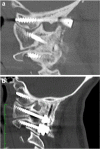

Objective: Condylar screw fixation is a rescue technique and an alternative to the conventional configuration of occipitocervical fusion. Condylar screws are utilized when previous surgical bone removal along the supraocciput has occurred which makes anchoring of a traditional barplate technically difficult or impossible. However, the challenging dissection of C0-1 necessary for condylar screw fixation and the concerns about possible complications have, thus far, prevented the acquisition of large surgical series utilizing occipital condylar screws. In the largest case series to date, this paper aims to evaluate the safety profile and complications of condylar screw fixation for occipitocervical fusion.

Methods: A retrospective safety and complication-based analysis of occipitocervical fusion via condylar screws fixation was performed.

Results: A total of 250 patients underwent occipitocervical fusions using 500 condylar screws between September 2012 and September 2018. No condylar screw pullouts, or vertebral artery impingements were observed in this series. The sacrifice of condylar veins during the dissection at C0-1 did not cause any venous stroke. Hypotrophic condyles were found in 36.4% (91 of the 250) cases and did not prevent the insertion of condylar screws. Two transient hypoglossal deficits occurred at the beginning of this surgical series and were followed by recovery a few months later. Corrective strategies were effective in preventing further hypoglossal injuries.

Conclusions: This surgical series suggests that the use of condylar screws fixation is a relatively safe and reliable option for OC fusion in both adult and pediatric patients. Methodical dissection of anatomical landmarks, intraoperative imaging, and neurophysiologic monitoring allowed the safe execution of the largest series of condylar screws reported to date. Separate contributions will follow in the future to provide details about the long-term clinical outcome of this series.